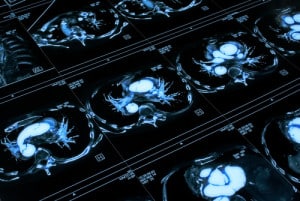

Will computers “see” better than radiologists?

Deep learning is finding a valuable place in autonomous vehicles, but according to a new report from Signify Research, the practice could create a $300 million medical imaging market by 2021.

While deep learning is predicted to grow rapidly, investment in other image analysis techniques will likely be flat over the next few years. In 2016, spending on medical image analysis solutions was less than $300 million, and is slated to more than double by 2021. In other words, deep learning alone will get more investment for medical imaging by 2021 than the entire analysis industry spent in 2016. Why are hospitals looking to get a boost from deep learning?

In many countries, there simply aren’t enough radiologists to possibly examine and make smart decisions about the images they receive throughout the day. According to Radiology Business, and an analysis conducted by doctors at the Mayo Clinic, medical imaging saw “explosive growth” in the mid-2000s. Between 1999 and 2010, the number of images from a CT scan increased from 82 to 679 images per exam. MRIs jumped from 164 to 570 images.